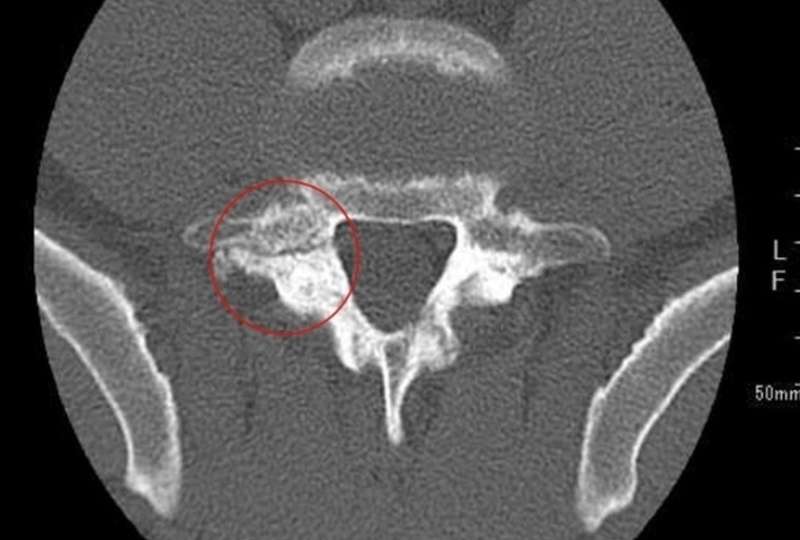

CT

→L5両側骨折あり、

L4右側にも骨折線あり

CT画像で腰椎分離症の終末期と診断しました。この症例は2019年6月から10 月にわたり、痛みの軽減を目的に体外衝撃波治療を施行しました。